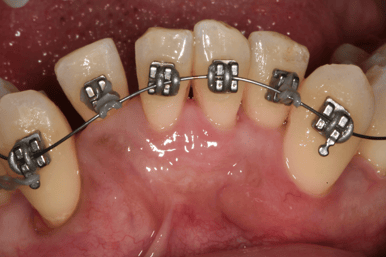

Orthodontiste

Orthodontie